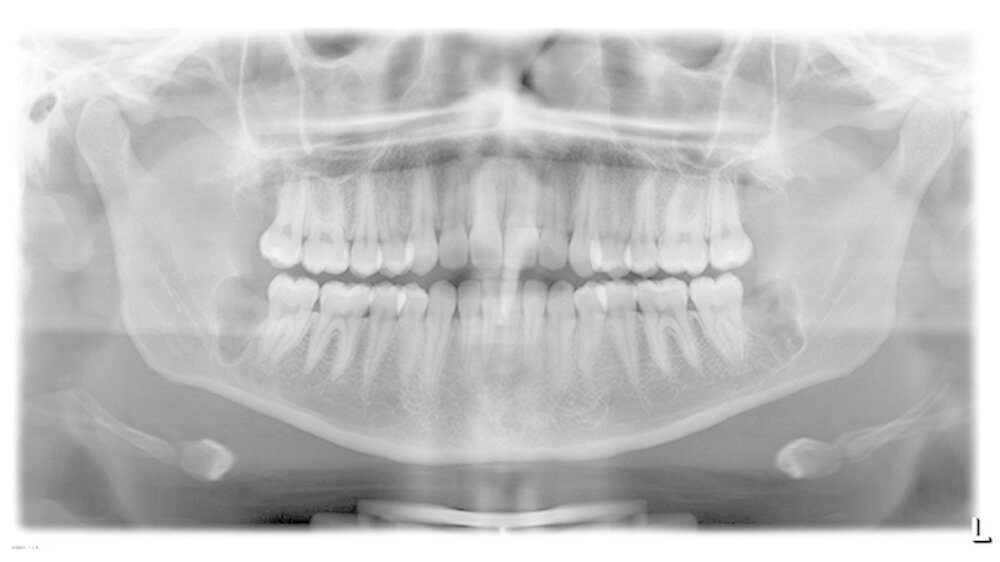

Eine 19-jährige Patientin wurde zur Entfernung der komplett retinierten verlagerten Weisheitszähne 18, 28, 38 und 48 überwiesen. Die Patientin war anamnestisch unauffällig, war aber Raucherin.

Aufgrund der engen Lagebeziehung der Weisheitszähne 38 und 48 zum Nervus alveolaris inferior (Abbildung 1) wurde zur weiterführenden Diagnostik eine digitale Volumentomografie (DVT) in der Praxis von Dr. Burkard Langenfeld in Friedrichshafen durchgeführt (Abbildungen 2 und 3).